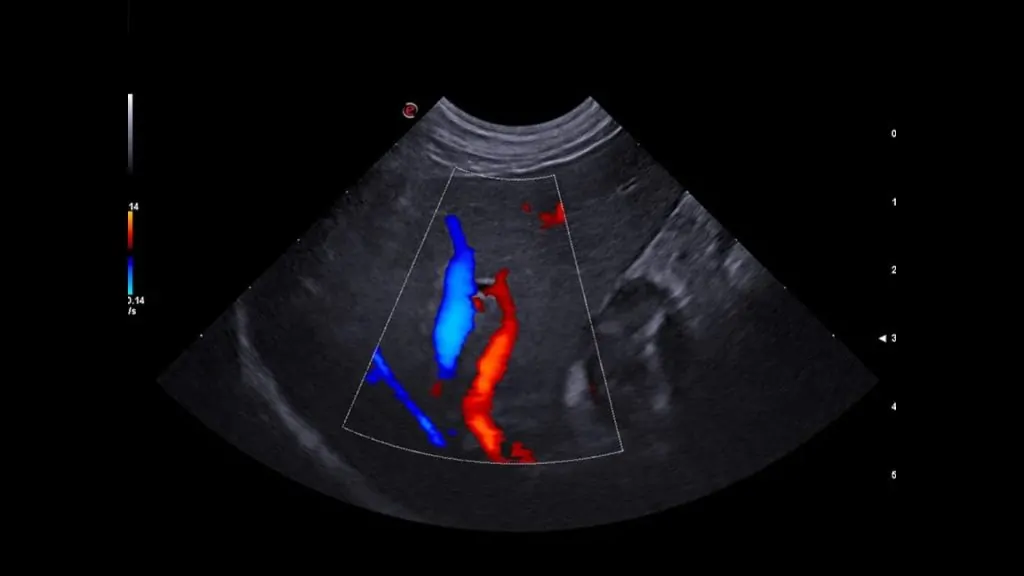

• Büyük damarlarda trombüs/emboli şüphesi gibi vasküler değerlendirmeler

• Gerekli görülen durumlarda Doppler USG ile kan akımı analizi yapılabilir.

Gerekli durumlarda Doppler ile direnç indeksi gibi parametreler incelenebilir.